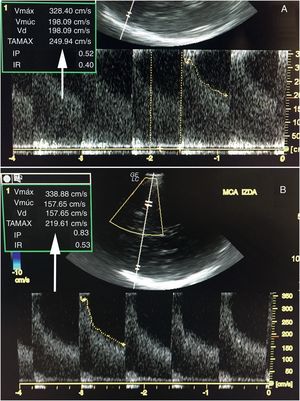

Las siguientes 48 h se caracterizaron por episodios fluctuantes de focalidad izquierda y evidencia de vasoespasmo grave por Doppler transcraneal (DTC), con velocidades medias de hasta 250cm/s en la ACM izquierda e índice de Lindegaard superior a 3. Al tercer día, se repitió la angiografía con nueva infusión de 8mg de nimodipino, esta vez con resultado parcial. La tomografía computarizada realizada posteriormente mostró una pequeña lesión isquémica frontal izquierda. Debido a la ausencia de mejoría clínica (plejía del brazo derecho y disfasia), se contactó con la Unidad del Dolor para la realización de un bloqueo del ganglio estrellado cervical izquierdo, que se llevó a cabo al cuarto día de ingreso bajo control de escopia (fig. 1). Se administraron 10ml de bupivacaína al 0,5% en bolo y se dejó colocado un catéter para la administración repetida del fármaco cada 12 h. A los 30 min del bloqueo, se objetivó recuperación parcial de la fuerza en el brazo derecho, mejorando la nominación de objetos. En ese momento, el DTC mostró una disminución de la velocidad media en ACM izquierda del 10% (fig. 2 A y B), que descendió de forma progresiva en las siguientes horas. Después de 3 días de tratamiento con bupivacaína (6 dosis), la paciente mantuvo una mínima claudicación braquial, sin alteraciones del lenguaje, consiguiendo la retirada del bloqueo cervical sin recidiva de los síntomas y con descenso de la velocidad por DTC hasta del 70% con respecto a su valor máximo.